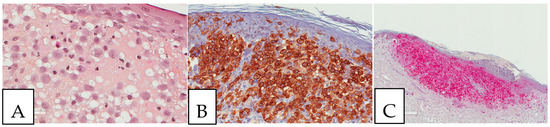

5. Pathologic Features